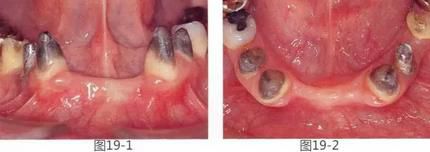

360截圖20170422142144525.jpg

圖19-1  將左下1,2,右下1,2拔除后4個(gè)月的正面照。

圖19-2  同時(shí)期咬合面照。佩戴臨時(shí)修復(fù)體后,由于易滯留食物殘?jiān)?,涂抹口紅困難而感到不滿。